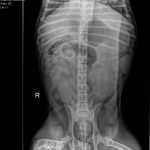

They Ate What?! X-ray Contest 2017They Ate This: Check out the winner, runners-up, and honorable mentions September 29, 2017 < Previous Entry Next Entry > Pages: 1 2 3 4 5 6 7 8 9 10 11 12 13 14 15 16 17